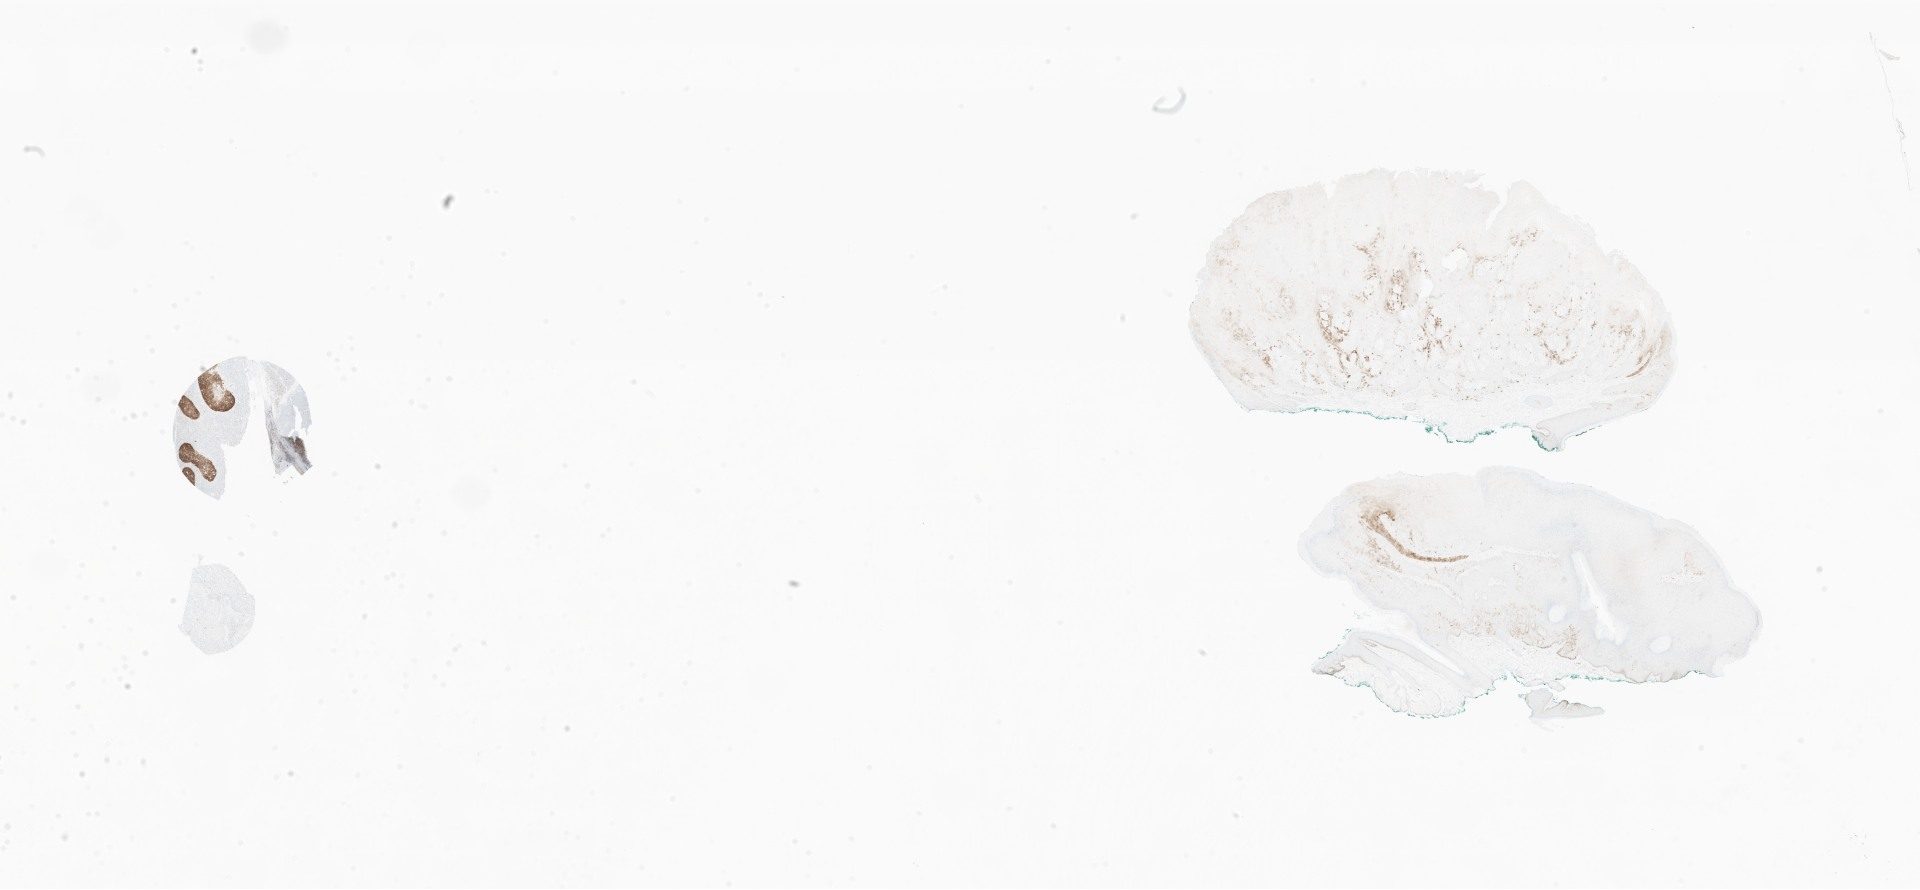

ki67.svs

80127

x

48338

@

40X